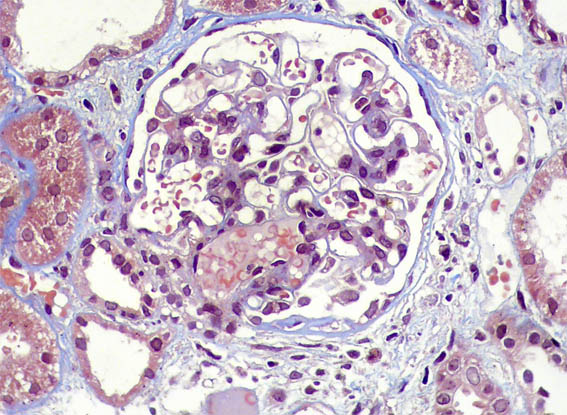

Figure 5. PAS, X400.